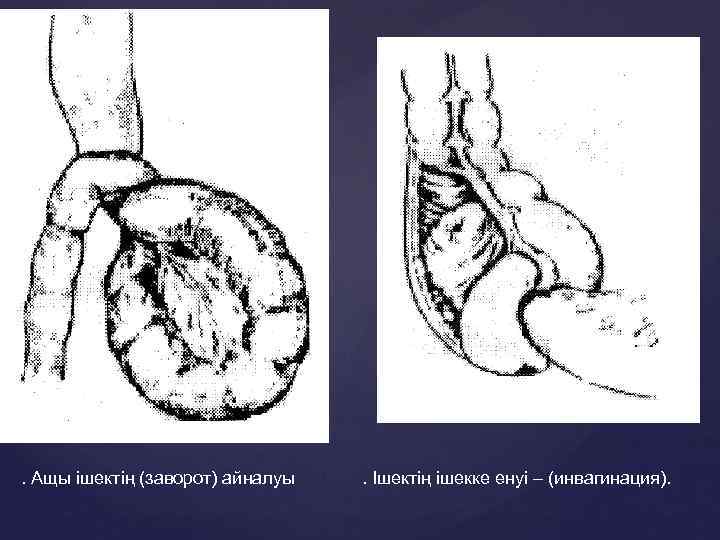

. Ащы ішектің (заворот) айналуы . Ішектің ішекке енуі – (инвагинация).